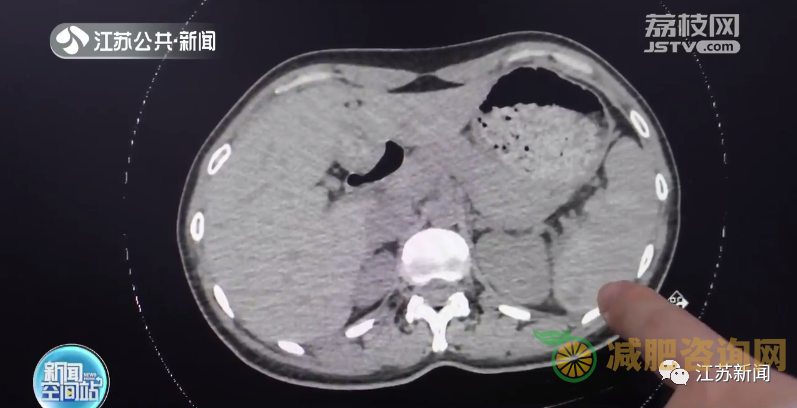

常州市第七人民医院胸心外科副主任医师俞文俊介绍:“查了CT,发现了刘女士脾脏有出血、腹腔有积液,考虑是脾破裂。但她这个脾破裂跟平时急性的破裂不一样,她是迟发性的脾破裂。”

医生介绍,摔倒导致迟发性脾破裂其实比较常见。脾脏出现小的损伤后,伴有持续性的出血,当出血量超过脾脏包膜的压力时就会发生破裂,造成腹腔内出血,严重时可能危及生命。